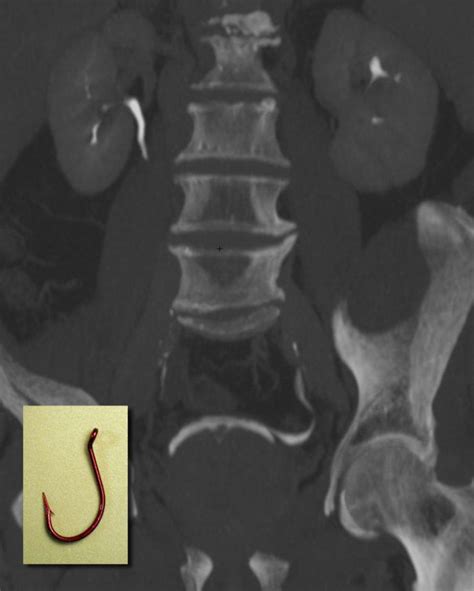

Alright, let’s get down to the nitty-gritty. The hockey stick deformity of the terminal ureters refers to a specific anatomical variation where the very end of the ureter, the tube that carries urine from your kidney to your bladder, takes on a distinctive curved shape. Imagine a hockey stick – the long shaft, then a sharp curve at the end. That’s precisely what the lower part of the ureter looks like in this condition when viewed through imaging. This isn’t necessarily a disease in itself, but rather a physical characteristic that can sometimes lead to problems. The ‘terminal’ part simply means the end portion of the ureter, right before it enters the bladder. So, we’re talking about that final stretch where the plumbing connects. This specific curvature can affect how urine flows from the kidney down to the bladder. Think of it like a kink in a garden hose; it might not completely block the water, but it can slow it down or cause pressure buildup. This subtle, yet impactful, change in the ureter’s path is the hallmark of this deformity. It’s a congenital condition, meaning people are usually born with it, though it might not become apparent or cause issues until later in life. Understanding this basic morphology is the first step in appreciating its potential clinical significance.

Figuring out if you’ve got a hockey stick deformity of the terminal ureters usually involves a few different diagnostic tools, and it often comes up when you’re already being investigated for urinary issues like recurrent UTIs or suspected reflux. The first line of investigation might be a urinalysis and urine culture to check for infection. If an infection is present, it’s treated, but if it keeps coming back, doctors will start looking for an underlying cause. Imaging studies are key here. An Intravenous Pyelogram (IVP), though less common now, or more commonly a Computed Tomography Urography (CT Urography) or Magnetic Resonance Urography (MRU) can provide detailed images of the urinary tract. These tests involve injecting a contrast dye into your vein, which then travels through your kidneys and ureters, making them visible on X-rays or scans. The characteristic curve of the terminal ureter will be apparent on these images. Another crucial diagnostic tool, especially for assessing function and reflux, is a Voiding Cystourethrogram (VCUG). This is a fluoroscopic study where a catheter is inserted into the bladder, and contrast dye is instilled. X-ray images are taken while the bladder is filling and during urination. This allows doctors to see if there’s any backflow of urine into the ureters (VUR) and to visualize the anatomy of the ureterovesical junction, including the hockey stick deformity. Ultrasound of the kidneys and bladder can also be useful, particularly for detecting hydronephrosis or identifying stones, and sometimes it can give hints about the ureteral anatomy. In some cases, if the diagnosis remains unclear or if surgical intervention is being considered, a cystoscopy might be performed. This involves inserting a thin, flexible tube with a camera (a cystoscope) through the urethra into the bladder. It allows the urologist to directly visualize the bladder lining and the opening of the ureters, confirming the anatomical findings. The combination of these imaging and procedural techniques helps build a comprehensive picture, leading to an accurate diagnosis of the hockey stick deformity and its associated complications.